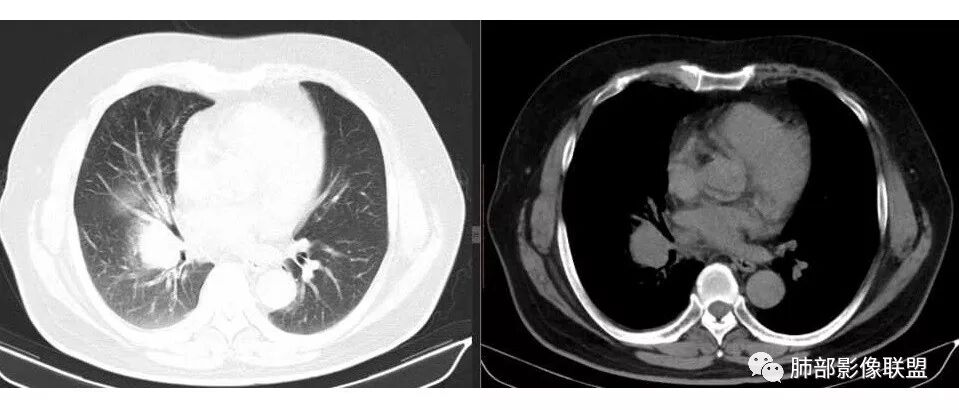

张帅: 患者以肢体无力就诊,既往有吸烟史,胸CT:右肺门占位性病变,密度不均,病灶内病灶内支气管明显狭窄,走行僵硬,病灶边缘光滑,呈浅分叶,未见明显毛刺,对中叶支气管明显挤压。右肺内可见散在片状实变影,前纵隔淋巴结明显肿大,内可见低密度区,2r 4r 7 10r淋巴结明显肿大。诊断考虑恶性方向,肺癌(小细胞)并纵隔肺门淋巴结转移?淋巴瘤?

水晶石头: 患者中老年男性,以四肢乏力为症状表现,有吸烟史。胸部CT:右肺上叶不规则结节,周围见磨玻璃影,小叶间隔增厚。同侧纵膈明显淋巴结肿大。综合考虑恶性。存在小病灶大转移,冰冻纵隔,且有内分泌症状,首先小细胞癌可能大。监测排外淋巴瘤。

支气管狭窄,壁有侵犯

局限性中央间质增厚,考虑癌性淋巴管炎

部分区域有结节感

南边: 例如这个病灶,如果是一个孤立的肿块,边界清晰,提示破坏性不强,不应该是包绕支气管,是推移到一边为主,这个表现为包绕,提示是多个病灶融合

宇宙星空: 肺门区及纵隔淋巴结肿大融合,支气管被包绕

1.右肺上叶不规则结节影,右肺门及纵隔多结节并形成巨大块影,密度均匀,沿途支气管明显狭窄。

原发灶小或隐匿,肺门纵隔淋巴结异常增大,所谓“娘小崽大”常见于肺小细胞癌!

2.右肺小叶间隔增厚伴微小结节,提示癌性淋巴管炎。